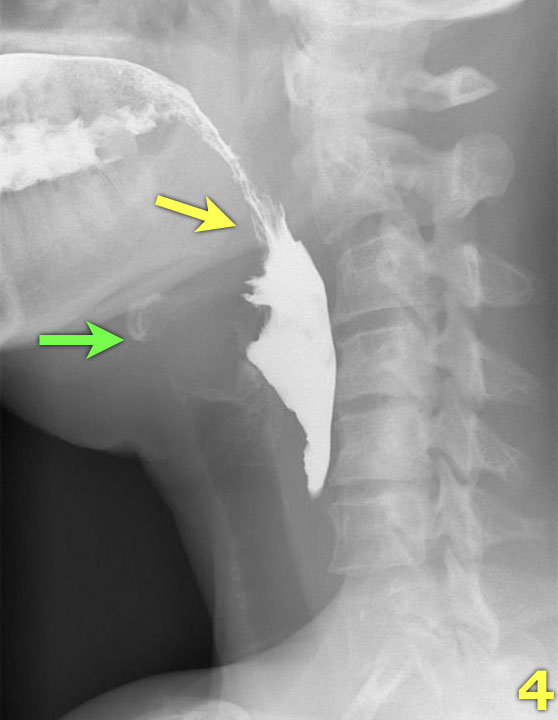

TRÁI: túi thừa nhỏ. GIỮA và PHẢI: túi thừa Zenker thực sự do đóng sớm của cơ nhẫn hầu (mũi tên vàng)

Túi thừa Zenker

Túi thừa Zenker luôn là hậu quả của rối loạn chức năng cơ nhẫn hầu.

Đóng sớm của cơ nhẫn hầu dẫn đến tăng áp lực trong hạ hầu, ngay phía trên cơ nhẫn hầu, khi sóng áp lực của các cơ khít hầu đẩy bolus xuống dưới.

Áp lực tăng này có thể gây phồng ra tại điểm yếu trên thành hầu sau (khe hở Killian).

Ban đầu sẽ tạo thành một túi nhỏ, theo thời gian có thể phát triển và hình thành túi thừa Zenker thực sự (Hình).